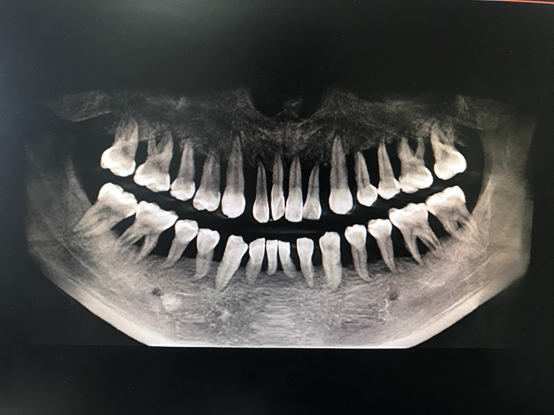

近日,25歲的小周碰到了一個大難題,他的牙“出問題了”,全口牙齒無法咀嚼,除了流食以外什么也不能吃。杭州師范大學(xué)附屬醫(yī)院牙周病診療中心醫(yī)生發(fā)現(xiàn),小周的牙齒情況類似于80歲的老太太,全口牙齒幾乎都是松動無法行使咀嚼功能。這意味著小周口內(nèi)牙齒幾乎都要拔除,全口牙沒有幾個能保留。

“我從醫(yī)這么多年也是第一次見到如此嚴(yán)重的牙周炎患者?!苯釉\醫(yī)生周矗說,從小周的口腔檢查中發(fā)現(xiàn),他的全口牙齒都有牙齦的膿腫,伴有嚴(yán)重的骨頭萎縮以及吸收,所有牙齒幾乎都是3度松動,并且口腔異味特別嚴(yán)重,牙齒上附著大量牙結(jié)石及食物軟垢。